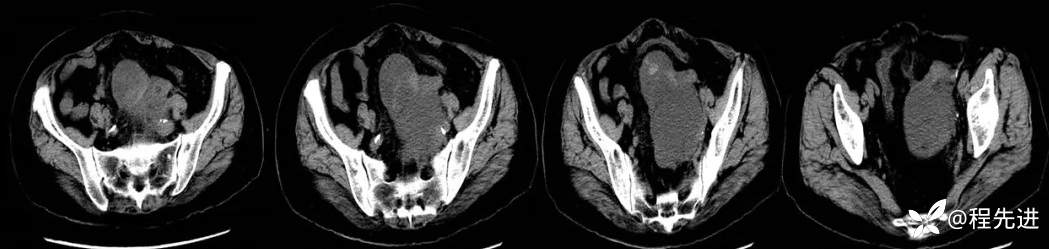

简要病史:4月前患者因腹痛数日

CT平扫+增强如下: